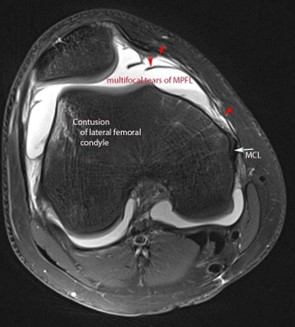

Fig 2: Rottura MPFL in RMN e relativo edema osseo del condilo femorale esterno